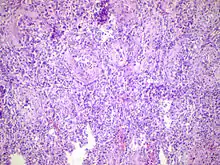

| Acute epididymitis with abundant fibrinopurulent exudate in the tubules. | |